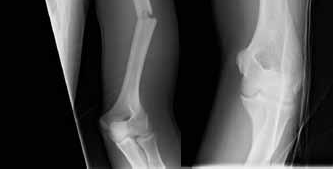

A 6-year-old girl falls from monkey bars and sustains a widely displaced extension-type supracondylar fracture of the distal humerus. On physical examination prior to reduction, she is unable to flex the interphalangeal joint of the thumb and the distal interphalangeal joint of the index finger, resulting in an inability to make an 'A-OK' sign. Which nerve is most likely injured?

Correct Answer: Anterior interosseous nerve (AIN)

Explanation:

The anterior interosseous nerve (AIN), a motor branch of the median nerve, is the most commonly injured nerve in extension-type supracondylar humerus fractures. It innervates the flexor pollicis longus (FPL) and the flexor digitorum profundus (FDP) to the index and middle fingers. Injury results in the inability to flex the IP joint of the thumb and DIP joint of the index finger, preventing the patient from making an 'OK' sign.